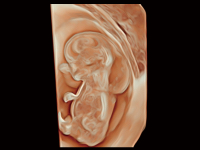

睿顏成像

多光源成像

S-Fetus? 鳳眼

S-Fetus? 鳳眼(A4C切面)